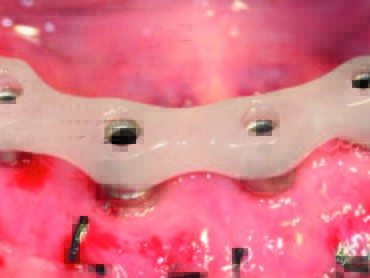

Nach Wundverschluss und einer Einheilphase von drei Monaten erfolgte die chirurgische Implantatfreilegung. Nach Entfernung sämtlicher Verschlusskappen wurden die entsprechenden Gingiva- oder Sulkusformer eingebracht (Abb. 15, 16). Zuvor wurde die Abformung⁴ (Abb. 17) mit einem A-Silikon in mittlerer Konsistenz für die Doppelmischtechnik in Kartuschen durchgeführt. Die einzelnen Abformpfosten wurden hierbei mit Pattern Resin LS in typischer Art und Weise verblockt, wie es in der Implantologie vielfach empfohlen wird⁵. Im nächsten Schritt erfolgte noch eine Vestibulumplastik zur Verbreiterung der Zone der Attached Gingiva. Parallel wurde im zahntechnischen Labor ein Meistermodell mit Zahnfleischmaske erstellt. Dort wurden das Meistermodell als auch die bestehende Unterkieferprothese des Patienten digitalisiert. Die gematchten Daten wurden an das ATLANTIS-Fertigungszentrum versandt. Auf der webbasierten Plattform ATLANTIS WebOrder wurden die patientenspezifischen Daten angelegt und vier individuelle Abutments bestellt. Zudem wurden die Art der gewünschten Restauration und das Material für den vorliegenden Patientenfall bestimmt: ATLANTIS Conus-Abutment Overdenture 5 Grad und Titan. Wenige Tage nach dem Versand der Daten wurde ein Designvorschlag für die konischen Abutments zugestellt, der im 3DEditor begutachtet und bis zu einem gewissen Grad bearbeitet werden kann. In der Maske des 3D-Editors können die Länge der Conus-Abutments (Margin Height), die mesial-distale Achse (MD Angle) sowie die fazial-linguale Achse (FL Angle) geändert werden. Die virtuelle Konstruktion der Abutments kann am Monitor in vielen verschiedenen Ebenen und Ausrichtungen begutachtet werden. Von Vorteil ist unter anderem, dass das Behandlungsteam das Set-Up (hier: die gescannte und vorhandene Prothese) einblenden und somit die Abutments in Bezug auf die angestrebte prothetische Versorgung beurteilen kann. In diesem Fall waren keine Änderungen notwendig. Nach Freigabe der Konstruktion wurden die ATLANTIS Conus-Abutments in Titan umgesetzt⁶.